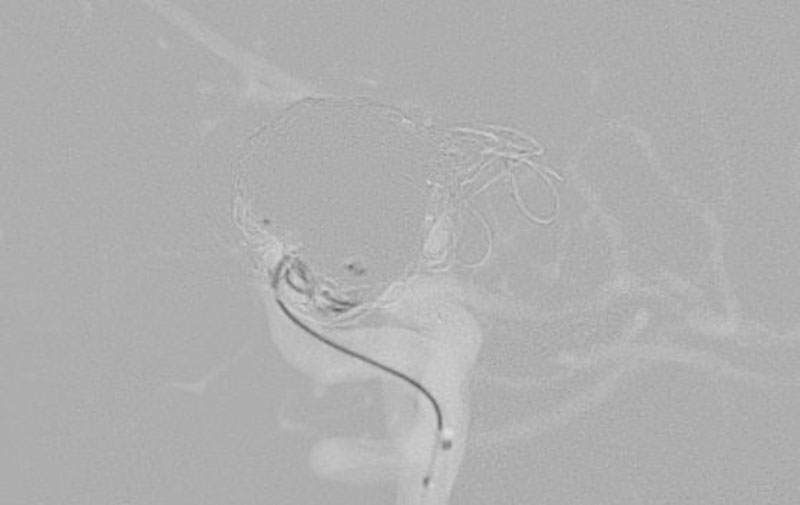

No.1628 手術中